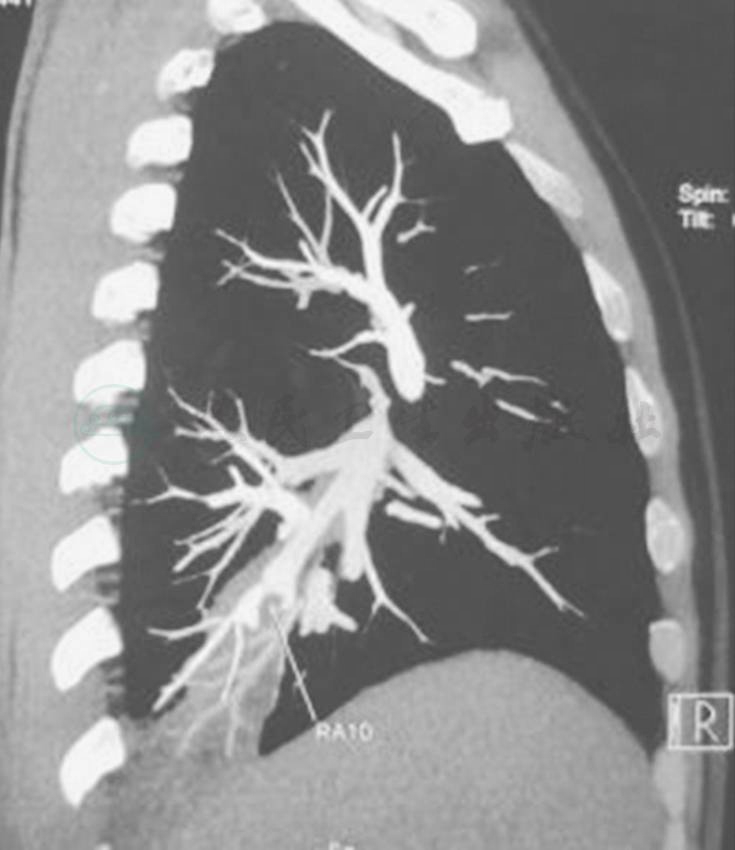

胸部CT示双肺多发结节、空洞影,左舌叶、右下叶大片渗出影(图1),一周后加重 (图2)。

图2 胸部CT表现(2011-08-18)

胸部CT显示双肺阴影较前增多、加重,并出现双侧胸腔积液,左侧明显